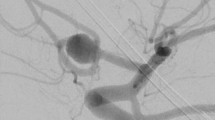

Currently, digital subtraction angiography (DSA) is considered the gold standard method to evaluate the CAC morphology and particularly the detection of possible areas of aneurysms [17]. When examining an AComA aneurysm, it is important to estimate the presence of a persistent MACC (2.3% PP) as this vessel becomes one of the draining arteries of the aneurysm [38]. Ogawa et al. [38] highlighted the significance of the persistent MACC coexisting with AComA aneurysm. The persistent MACC courses parallel to and posterior to the pericallosal artery, and this is why it can be easily damaged intraoperatively [38]. Precisely, they identified that in 81.5% of their studied cases, the aneurysm was formed at the AComA trifurcation, ACA A1 segment, and the MACC which makes the surgical manipulations extremely difficult [38]. In this early study (1990), it was indicated that a bifrontal craniotomy and an interhemispheric approach are the best techniques for aneurysmal surgery, due to the wide operative field and the ability to understand the AComA anatomy and adjacent structures [38]. However, nowadays, the pterional approach is popular for the treatment of AComA aneurysms [53]. Overall, it has been proved that smoking, A1 segment asymmetry, pulsatility index in the A1 segment, and the angle between the A1 and A2 segments are independent risk factors for the development of an AComA aneurysm [29]. Alfano et al. [1] observed a significant association between vessel’s bifurcation and aneurysm development (for example, Y-shaped, or V-shaped AComA) due to high wall shear stress. Even recovery levels from vascular diseases, like ischemic stroke patients, may be altered due to the CAC variants. Chuang et al. [6] identified that patients with a typical CAC have earlier improvement than patients with a variant circle in ischemic stroke patients. Especially, in the anterior brain circulation where cerebral infracts most commonly occur, variations are of great importance particularly during surgery [50]. Except for aneurysm formation, the CAC variants have been associated with mental diseases. Blackburn [3] in 220 patients with mental diseases, identified a predominance of variant circles among the mentally diseased. Blackburn [4] analyzed 42 cases of ACA fusion in a total of 400 patients with mental diseases (10.5%), they observed that fusion occurred in all forms of diseases, possibly a little more frequent in dementia. Kamath [25] reported a higher incidence of variant CAC in mentally diseased patients. As intriguing as these findings are, they were based on assumptions and are not definite.